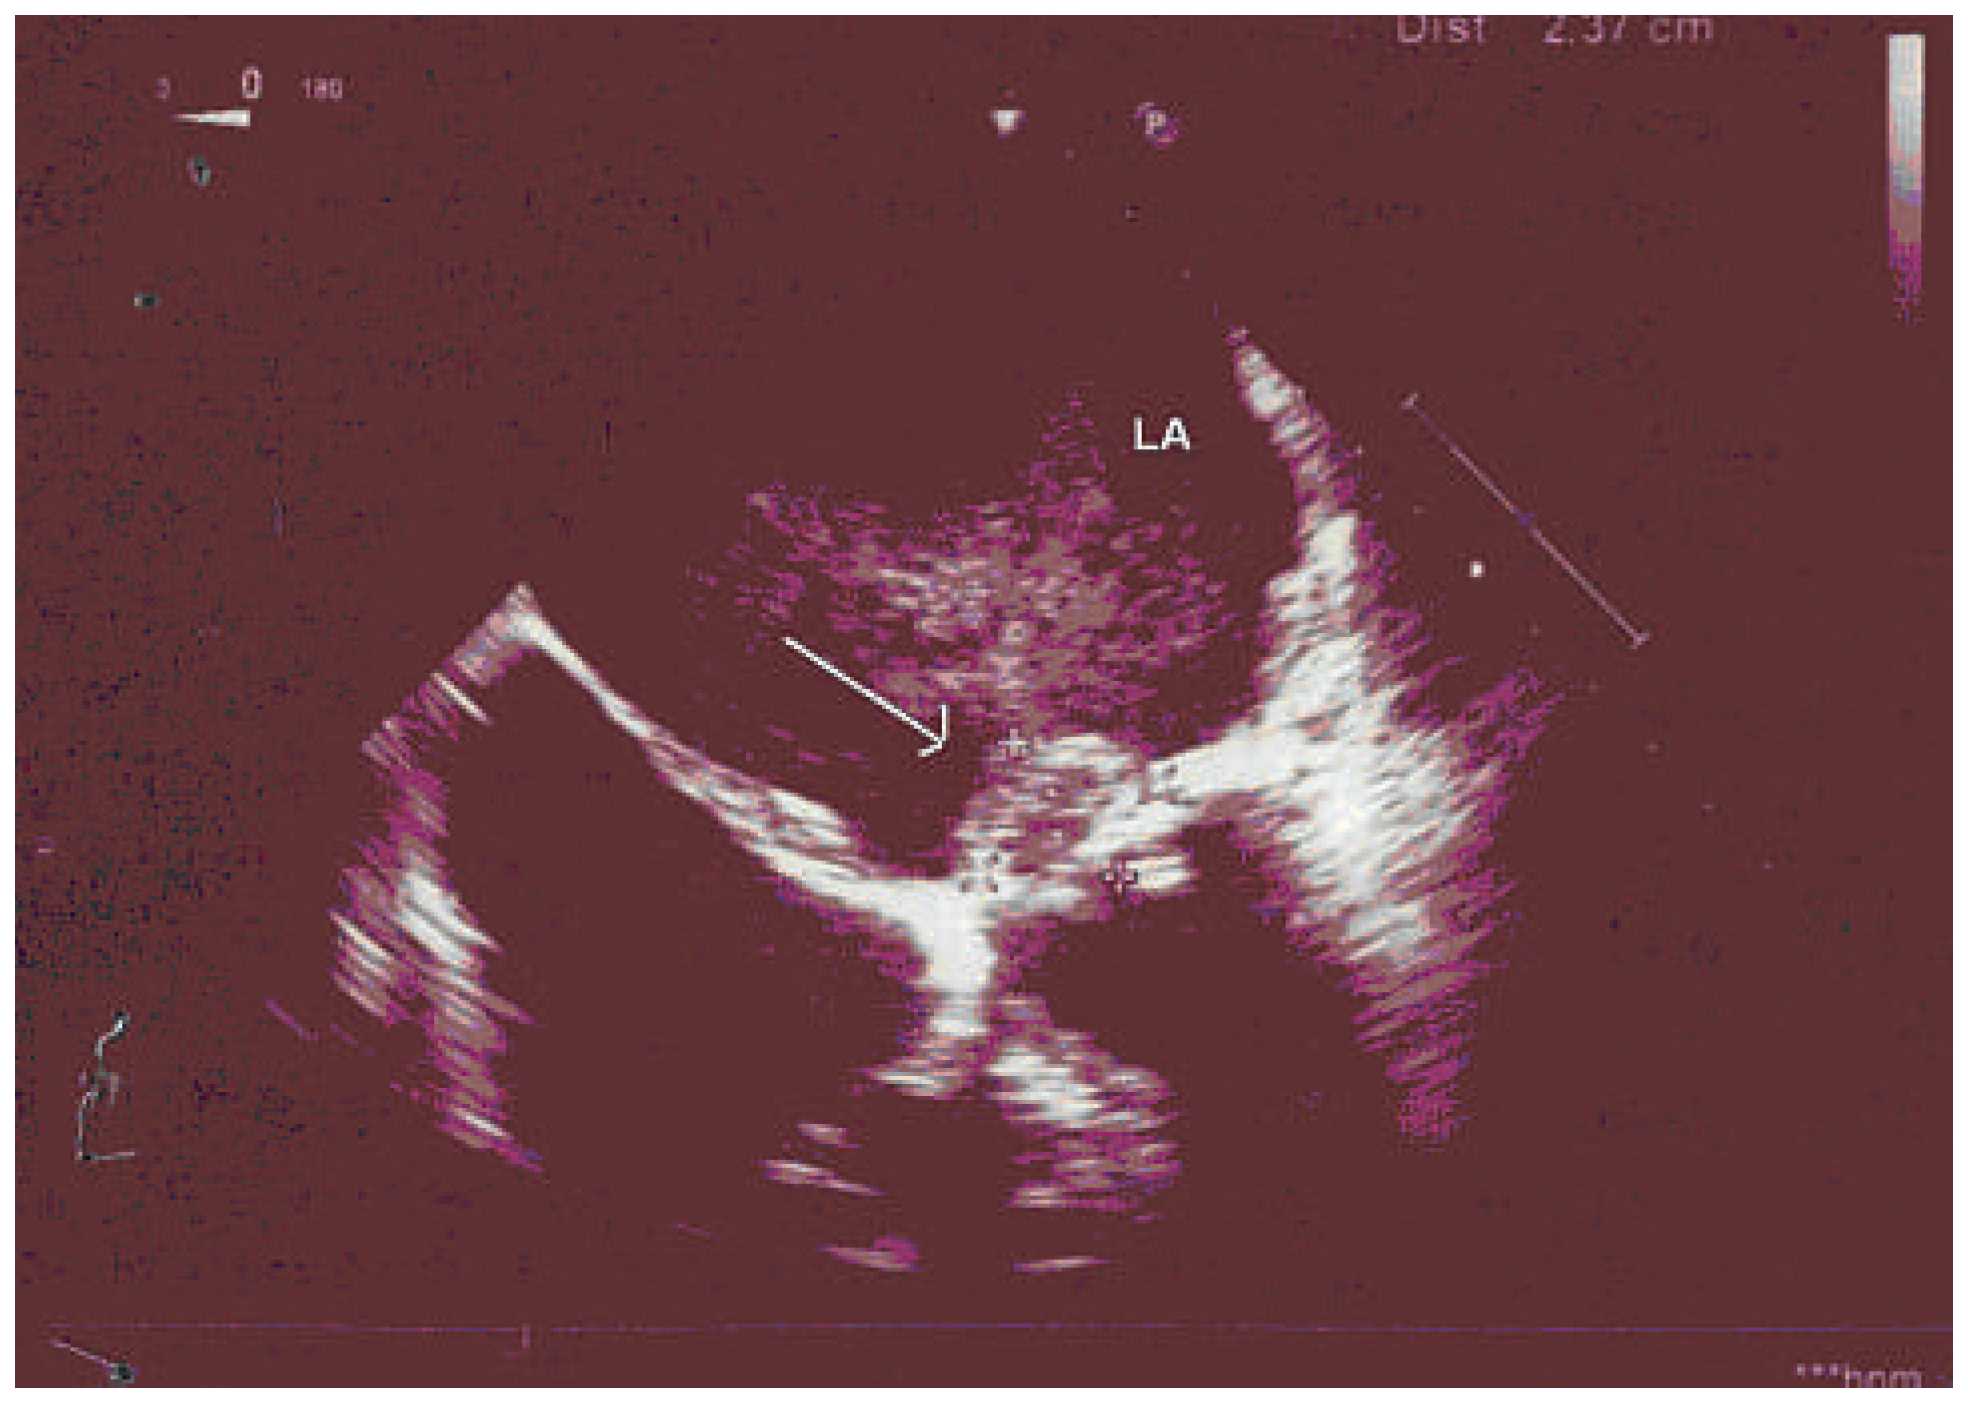

Transoesophageal echocardiography (Figure 1) showed two masses in the left atrium; a large lesion (20 × 23 mm) adherent to the free edge of the anterior mitral leaflet causing severe functional mitral obstruction with a mean gradient of 20 mm Hg, and a further lesion occluding the left appendage extending to the side wall and to the roof of the left atrium (46 × 20 mm).

Figure 1. Transoesophageal echocardiogram. Note an echodense mass adherent to the anterior mitral leaflet.